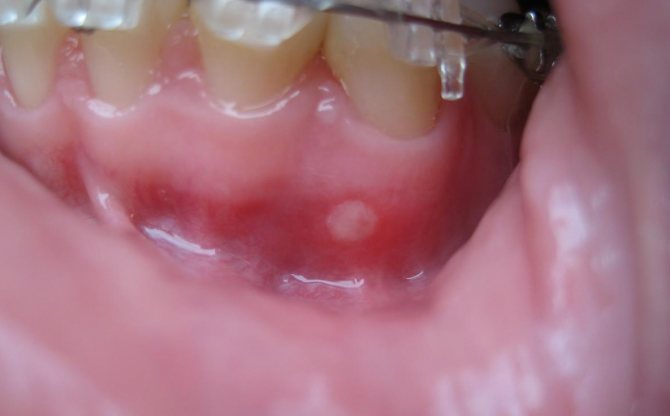

- Афтозный стоматит. Может быть вызван вирусными или бактериальными инфекциями, аллергическими реакциями, болезнями ЖКТ или даже гормональным дисбалансом в организме. Сопровождается появлением во рту круглых белых бляшек с красными ободками, которые без надлежащего лечения могут превратиться в серьезные язвы.

Афтозный стоматит локализуется под нижней губой, на языке и щеках, у основания десен (как на фото). Язвы – небольшие по размеру красные опухоли, которые припухают и «спадают» в течение дня. Когда такие образования саморазрешаются, их поверхность покрывается желтой или белой коркой, края язв четко очерченные, воспаленные. Изъявления при данной форме стоматита затягиваются в течение 2 недель, шрамов и рубцов на слизистой после них не остается. Общие симптомы беспокоят редко, за один раз на слизистой может появиться одна или несколько язв.